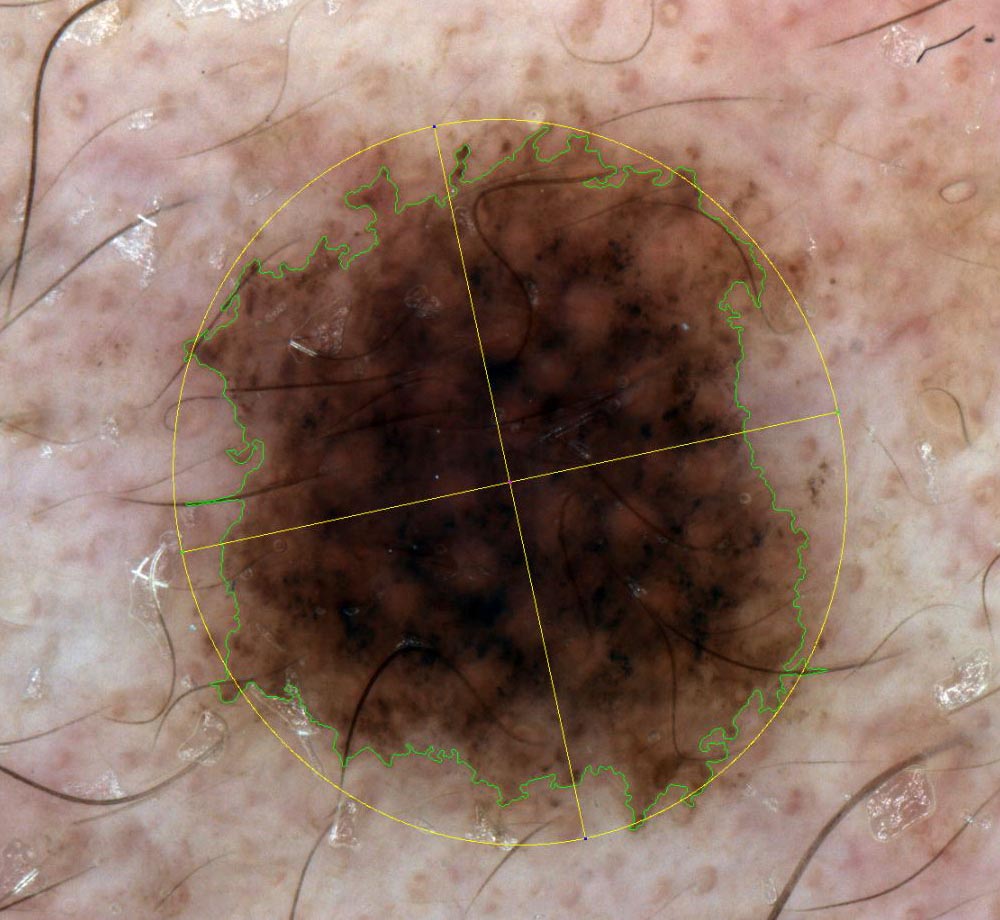

Segmentazione

La funzione di segmentazione determina il bordo della lesione i,dentificato da una curva di Jordan che separa l’area della lesione dallo sfondo.

La segmentazione manuale o automatica a seconda delle esigenze del clinico, segna il confine della lesione cutanea in tempo reale, rilevando il contorno della lesione, il suo centro, il suo orientamento e l’ellisse che si approssima all’intero neo.

Analisi

La funzione Segmentazione attiva l’analisi ABCDE su un’immagine di una lesione cutanea.

L’analisi ABCDE di IRSkin fornisce al medico informazioni quantitative riguardanti la morfologia e le caratteristiche pigmentarie della lesione cutanea.

Le funzioni di analisi ABCD, insieme alla possibilità di analizzare l’evoluzione di una lesione mediante la Body Map, forniscono informazioni quantitative e qualitative che possono aiutare il medico a migliorare la sua analisi ABCDE standard. Apparirà sullo schermo la schermata di analisi ABCD, insieme a i seguenti parametri numerici:

ASIMMETRIA:

Simmetria rispetto l’asse maggiore (percentuale di simmetria della pelle segmentata rispetto al suo asse maggiore di inerzia)

Simmetria rispetto l’asse minore (percentuale di simmetria della pelle segmentata rispetto al suo asse minore di inerzia)

Simmetria rispetto al centro (percentuale di simmetria della pelle segmentata rispetto al suo baricentro)

Simmetria media (media delle tre simmetrie precedenti)PARAMETRI DEL CONTORNO

Fattore di forma (quantità numerica che misura la complessità del contorno di una forma rispetto alla sua area: è proporzionale al rapporto tra l’Area della lesione cutanea e il quadrato del suo Perimetro. I piccoli valori del Fattore di forma indicano che la lesione ha un confine articolato)

Circolarità di Haralick (quantità statistica che misura la somiglianza di una forma con un cerchio) I grandi valori della circolarità dell’Haralick indicano che la lesione ha un’elevata circolarità

Ellitticità (quantità numerica che misura la somiglianza di una forma con la sua ellisse inerziale) I grandi valori di ellitticità indicano che la lesione è simile alla sua ellisse inerziale)

Eccentricità (quantità numerica che misura il rapporto tra gli assi inerziali di una forma: valori elevati di Eccentricità indicano una estesa lesione cutanea)COLORE:

Colore dominante (grafico che indica la distribuzione dei colori prevalenti della lesione cutanea)

Visualizzazione zone di colore(dei colori prevalenti della lesione cutanea e dei suoi assi inerziali)

Colore Entropia (quantità statistica, definita dal Team IRSkin, che misura le variazioni di colore della lesione cutanea tra i suoi quattro quarti)PARAMETRI DIMENSIONALI (espressi in millimetri):

Diametro (distanza massima tra due punti di una lesione cutanea)

Area (misura dell’area coperta dalla lesione cutanea)

Perimetro (misura della lunghezza del confine della lesione cutanea)

Lunghezzaì(misura della lunghezza dell’asse maggiore della lesione cutanea)

Altezza (misura della lunghezza dell’asse minore della lesione cutanea)